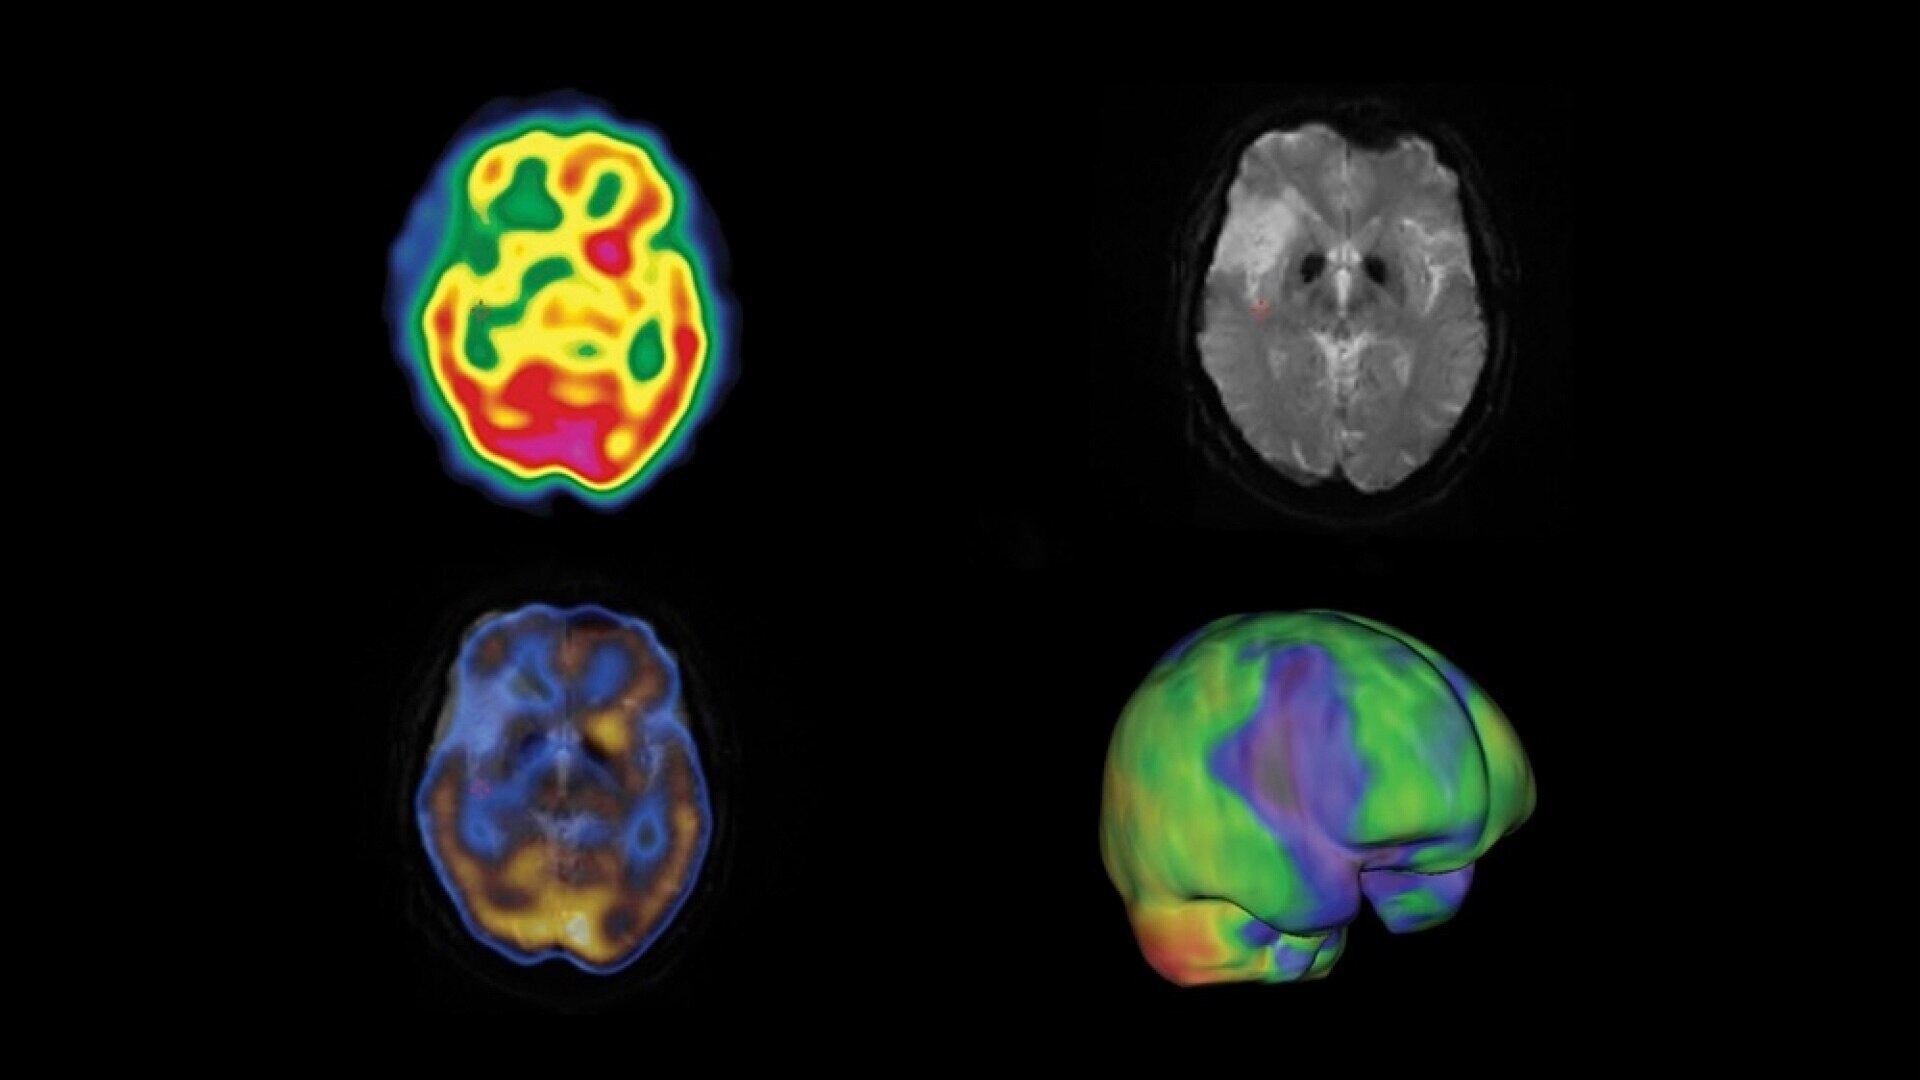

See everything clearly now

As molecular imaging continues to move toward the development of disease-specific diagnoses and increasingly personalized care, resolution is important. Early disease detection is only possible with a high system resolution that enables visualization of finer anatomic detail.

The resolution to discover something new

With direct conversion detection, NM/CT 870 CZT has substantially improved system resolution⁴ by eliminating the signal loss and noise that comes with analog detection technology. It also uses a registered collimation design that aligns each collimator hole with a single detector pixel. This design eliminates the impact of collimator resolution that would normally affect the overall system resolution. The result is an improved contrast-to-noise ratio⁵ and spatial resolution down to 2.8 mm.⁶